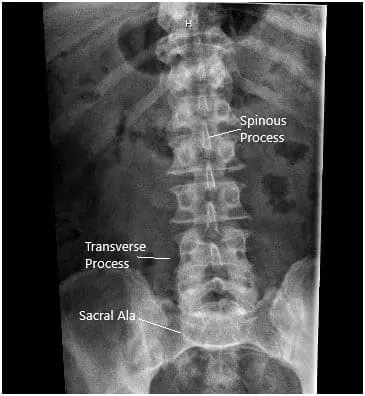

X-ray in AP and Lateral views demonstrated narrowing of the L5-S1 Disc